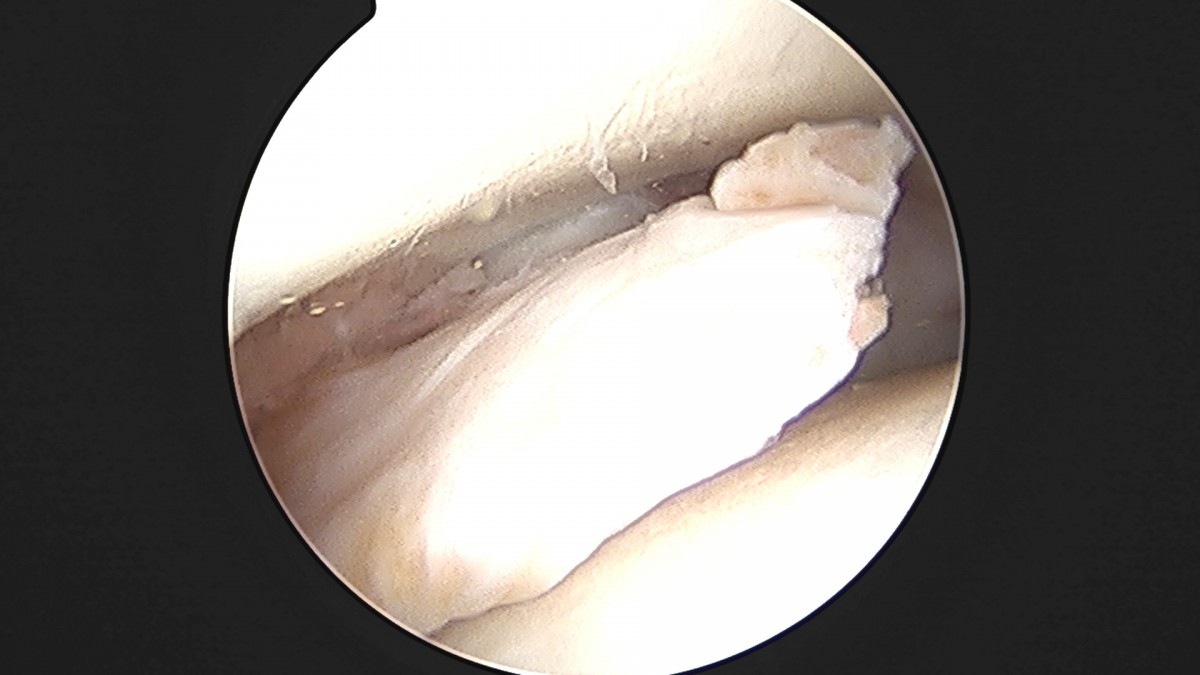

이재상원장님 발목 활액막 절제술 및 인대 봉합술 정보O 환자

dae765e4d9ac96aee867c9d6292d8784_1758003797_7751.jpg